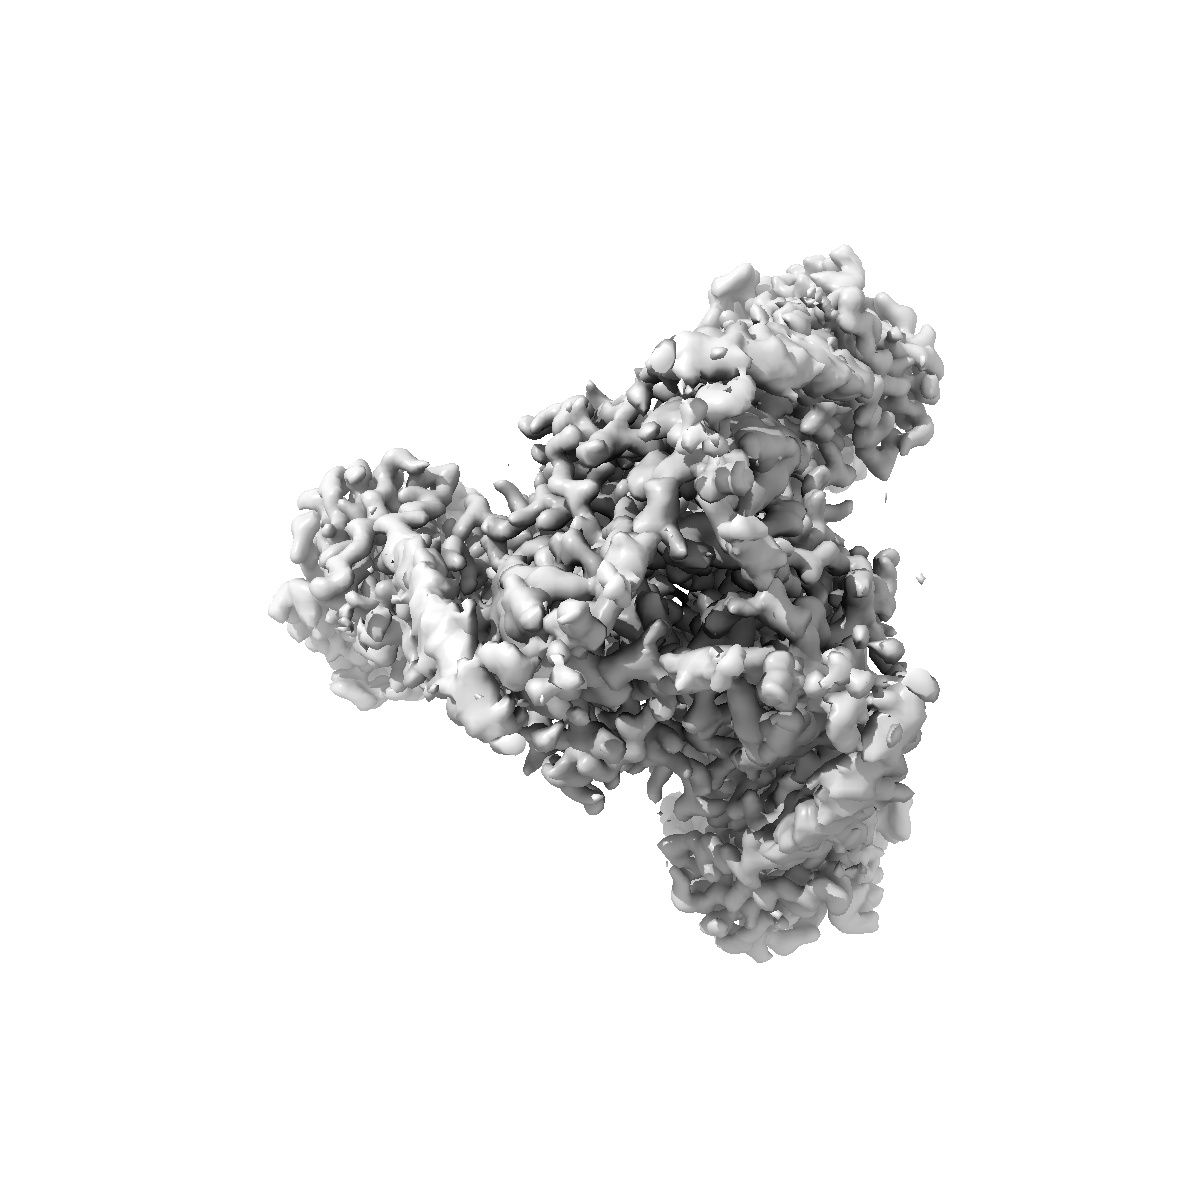

Cryo-EM structure of post-fusion EBV gB in complex with AMMO2 fab

Sample Organism: human gammaherpesvirus 4, Homo sapiens

Fitted models: 9yka

Deposition Authors: Chou CW, McCool RS, McLellan JS